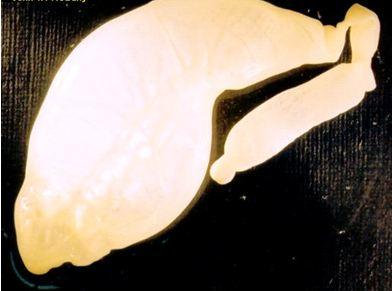

| 4. Echinococcus granulosus

This is a very short dog tapeworm, whose main significance is that the larval stage forms large multiple hydatid

cysts in the intermediate hosts, including humans. These cysts are located in the liver and lungs and can grow to a very large size indeed. People living in close association with dogs are especially at risk.

Coenurus cerebralis, the larval stage of Taenia multiceps multiceps is usually found in the brain or spinal cord of sheep or goats. The animals are normally emaciated and anaemic. Cysts may also be found in the lungs and liver.